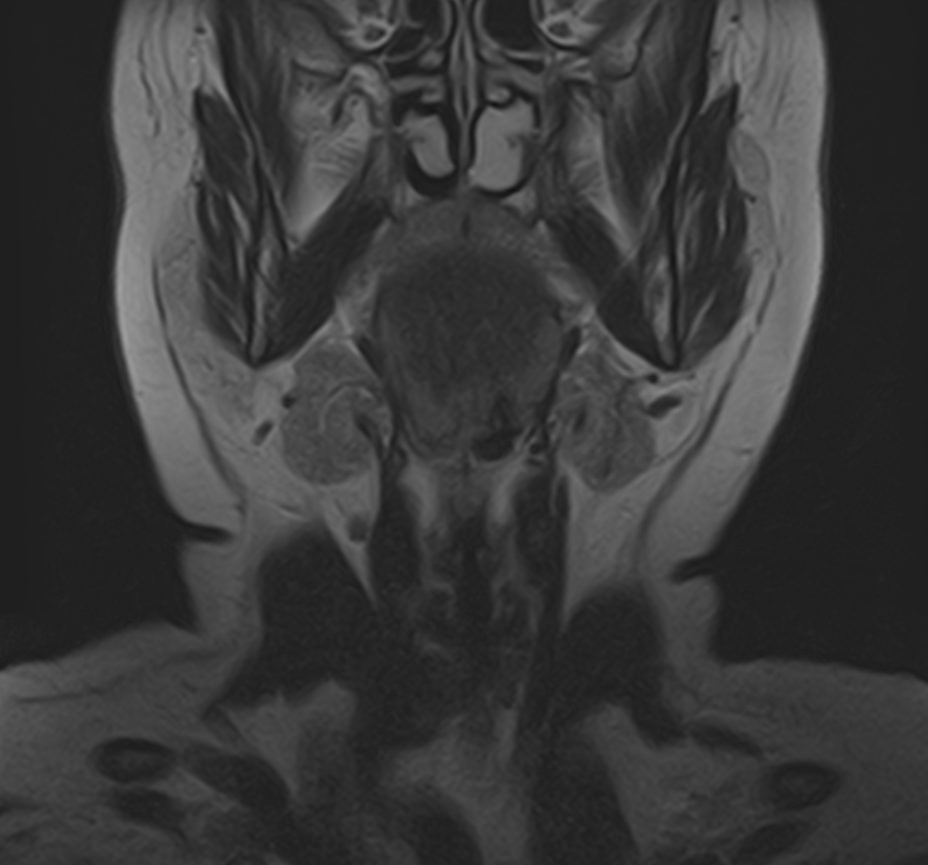

Магнитно-резонансная томография на сегодняшний день является наиболее информативным исследованием слюнных желез. Метод позволяет получить изображения мягкотканных структур с высокой детализацией, при этом отсутствие вредного ионизирующего излучения обеспечивает безопасность процедуры и позволяет проводить ее неоднократно по мере необходимости. Это бывает важно для оценки эффективности проводимого лечения.

В нашей клинике МРТ слюнных желез выполняется на высокопольном томографе экспертного класса TOSHIBA VANTAGE TITAN 1,5 Тесла. Аппарат производит сканирование в трех различных плоскостях в виде тончайших послойных срезов с шагом от 1 мм. Высокая индукция магнитного поля, используемая в аппарате, обеспечивает превосходное качество изображений. Кроме того, с помощью инновационных компьютерных приложений реконструируются объемные изображения исследуемой зоны, что улучшает визуализацию и повышает точность и достоверность диагностики.